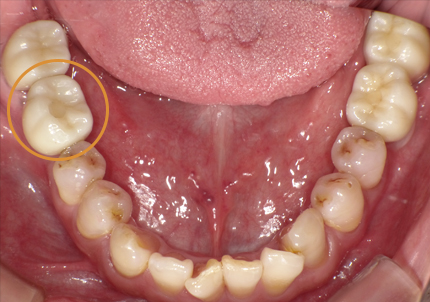

3.前回治療後5年経過(2021年2月)

【左下ブリッジ5番6番歯根破折の為要抜歯】

【左下5番ソケットシールドテクニック】

【ソケットシールドテクニックにて頬側骨の形態を維持する (右の様な骨のへこみを作らない)】

※ 通常、ソケットシールドテクニックは前歯部領域に用いるが小臼歯部でも採用しました

4.左下5番ソケットシールドテクニック

【ソケットシールドテクニックにより保存した歯牙片の内側にインプラントを埋入するCTシミュレーション】

【上記シミュレーションにて作製したガイドを用いたインプラント埋入】

5.インプラント埋入(2021年6月)